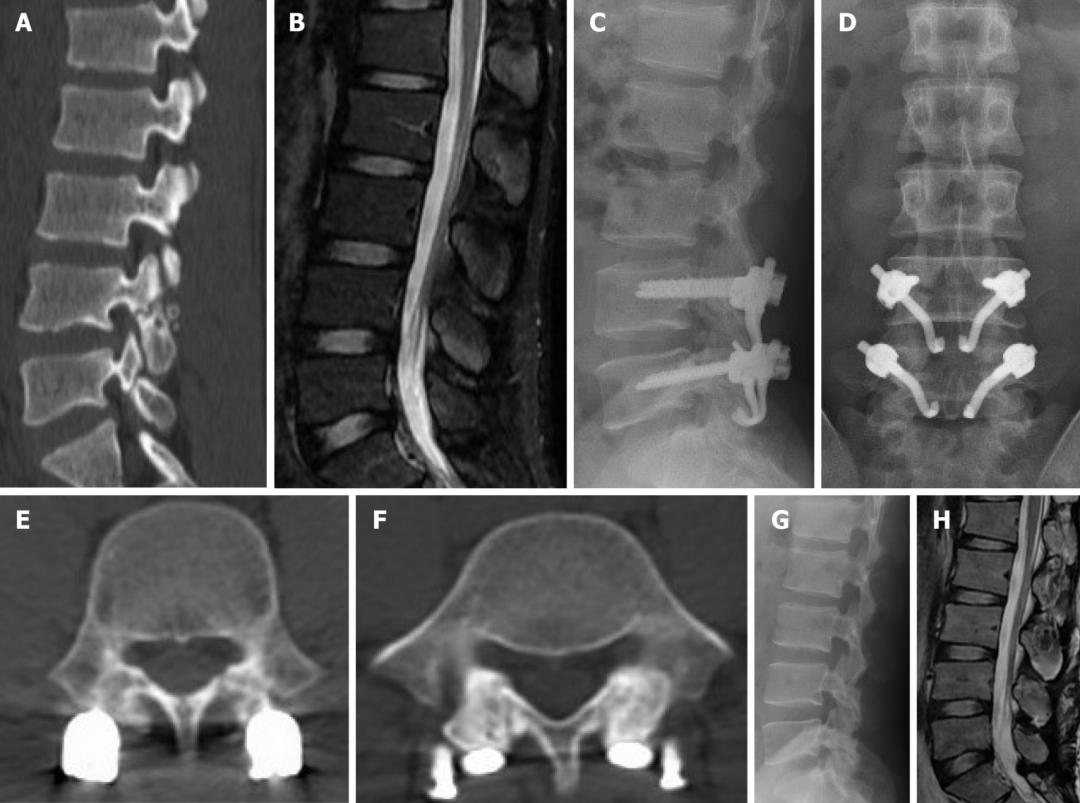

2019年国内解放军总医院第七医学中心李放教授团队。根据临床特点和影像学表现将所有病例分为3型:

• A型为单纯型峡部裂,无椎间盘突出及腰椎滑脱;

• B型为峡部裂伴有轻度椎间盘突出或I度滑脱,无神经压迫症状及体征;

• C型为峡部裂合并I度或Ⅱ度滑脱并椎间盘突出同时有神经压迫症状及体征。

并建议保守治疗无效的青年战士A、B型腰椎峡部裂病例采用椎弓根螺钉固定,峡部自体髂骨原位植骨融合率高,效果好,C型战士峡部裂则宜采用后路椎间植骨融合椎弓根螺钉内固定术。